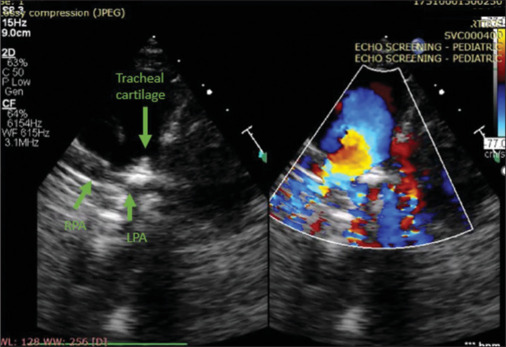

Imaging of a baby with recurrent airway infections.

Stridor, choking episodes and recurrent respiratory infections are common causes of referral for echocardiographic evaluation of the cardiovascular system. Vascular anomalies are rare but important causes of airway symptoms and/or feeding difficulty in young infants and should be carefully evaluated during echocardiogram.